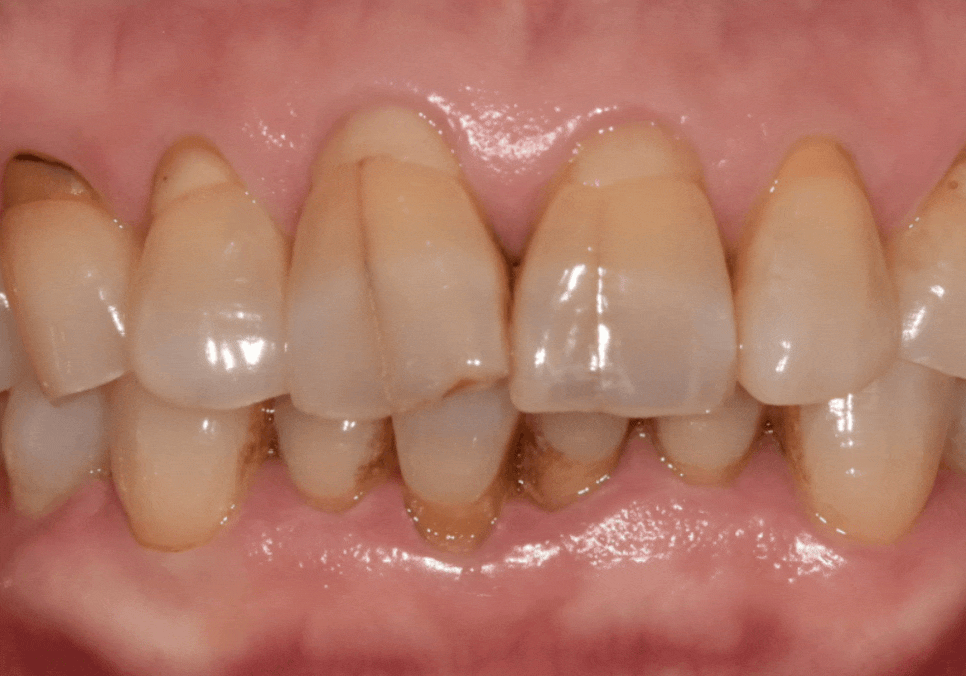

251229 (전) 260114(후)

이번 환자분 역시 옆 치아와 이질감이

전혀 느껴지지 않도록

자연스러운 지르코니아로 완성해 드렸습니다.^^

260114